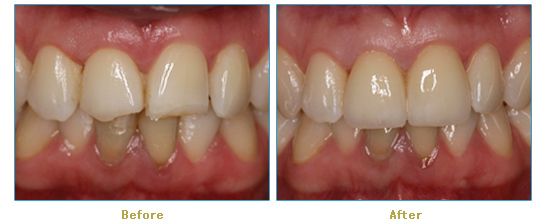

Dr. Cabianca has restored hundreds of smiles through the latest techniques in restorative and cosmetic dentistry. The following before and after photos document a few such cases in which Dr. Cabianca has replaced and reshaped teeth to produce wonderful smiles. Click on any of the images below to view larger versions of the photos.